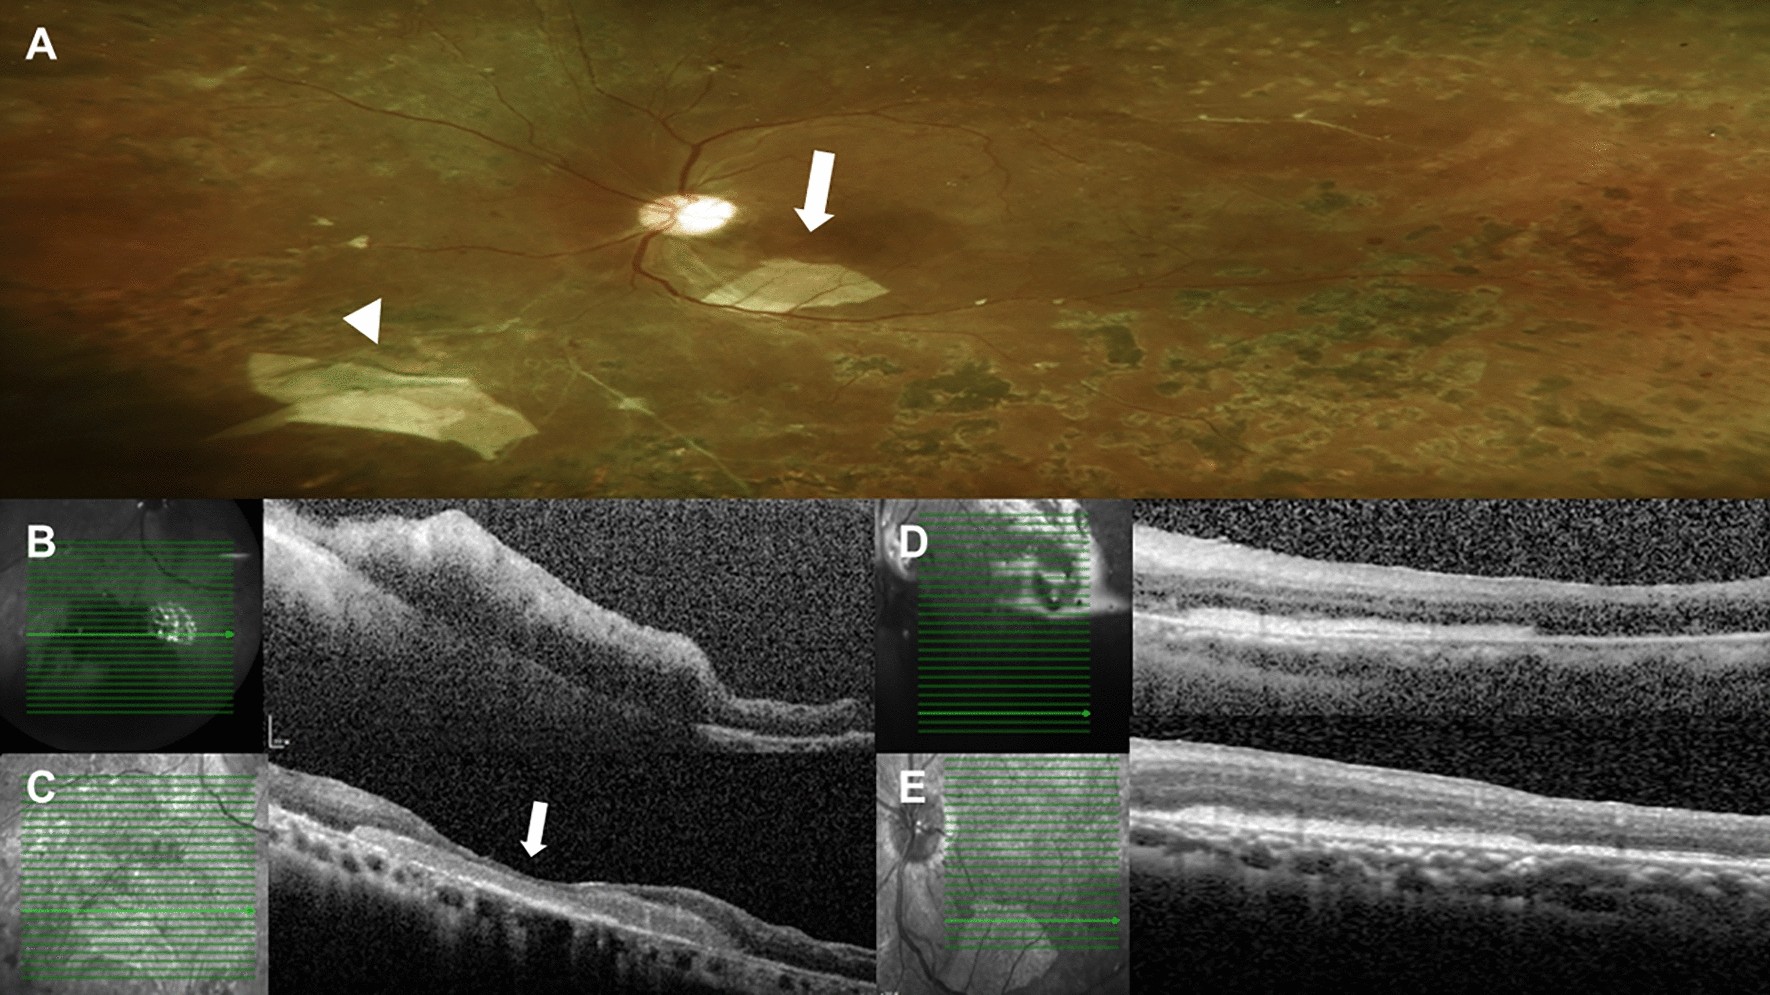

Figure 2

Postoperative color fundus photograph and serial optical coherence tomography (OCT) exams of case 7. (A) Color fundus photograph showed the one large retinal break securely covered by a human amniotic membrane (hAM) graft (arrow head). Also, there was one pice of hAM dislocated at the subretinal space within the vascular arcade intraoperatively (arrow). (B) Ten days after surgery, OCT scans over the location of retinal break showed the hAM graft covering the large break. (C) Six months later, follow-up OCT showed marked retina and glial tissue growing to cover the retina defect (arrow). And the graft remained stable without change in size. (D) Ten days after surgery, OCT scans of the dislocated subretinal hAM graft showed a sheet of hAM under the retina. (E) Six months later, the follow-up OCT revealed that there was no atrophy of the retina over the amniotic membrane. The retina structure remained intact and even more partial recovery of ellipsoid zone of the previous detached retina was observed.